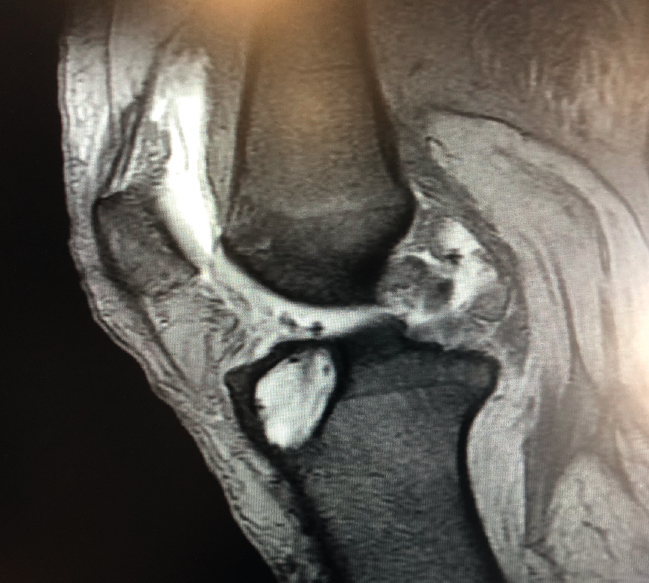

Un diagnóstico y una planificación correctos son fundamentales. En caso de rotura de plastia del LCA (Figura 3), se hace obligatoria, además de una detallada exploración, un correcto estudio radiológico completo que incluya radiología convencional y resonancia magnética (RM) –estudio de lesiones acompañantes o degeneración previa–. En ocasiones en donde la anamnesis/exploración lo justifique, pueden ser también necesarias telemetrías de extremidades inferiores, radiología forzadas (si existiera inestabilidad mediolateral) o tomografía axial computarizada (TAC) –valoración de la posición y la calidad de los túneles–.

Figura 3. Rotura de la plastia del ligamento cruzado anterior.